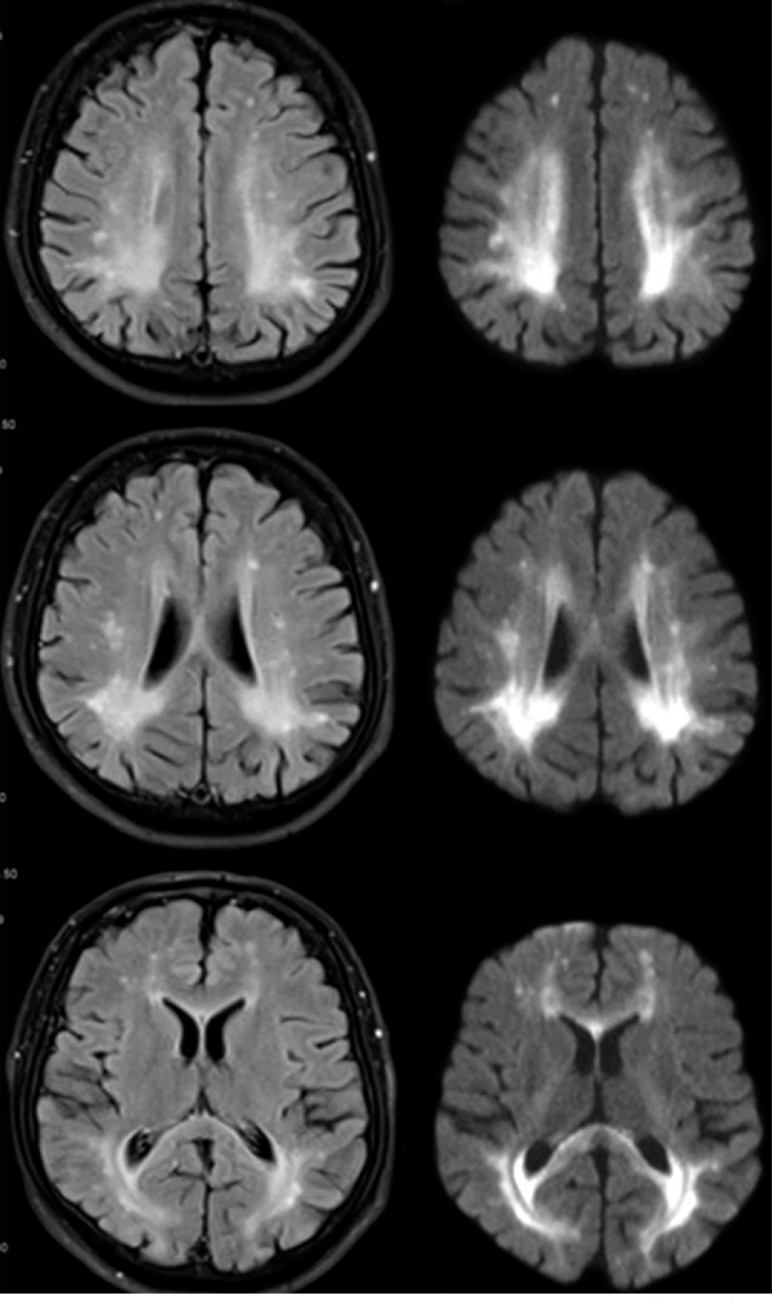

Neurological manifestations in an adult with phenylketonuria.